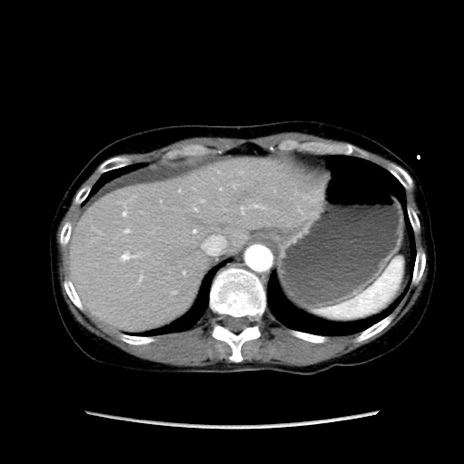

症例32(横断像)

【症例】40歳代 女性

【主訴】上腹部痛、嘔気・嘔吐

【現病歴】約9時間前頃から急に上腹部痛、嘔気、嘔吐が出現。改善しないため救急要請。

【既往歴】子宮頚癌(広汎子宮全摘術、放射線療法)、腸閉塞

【身体所見】腹部:平坦、軟、腸雑音亢進、上腹部を中心に腹部全体に圧痛あり。

【データ】WBC 8400、CRP 0.03